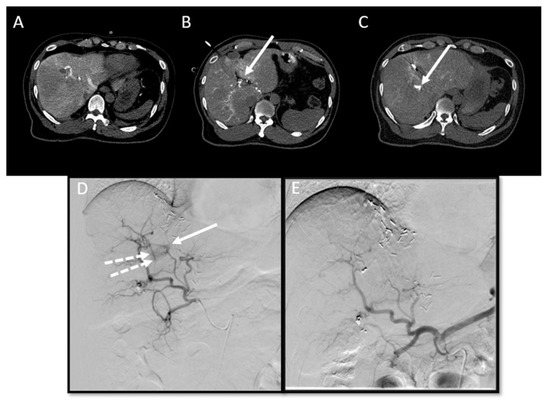

| 1 | 20 mm | Common hepatic artery | 15–20 mL Visipaque™ | Emprint™ Microwave Ablation System, Medtronic-Covidien, Boulder, CO, USA | MD Anderson, Houston, TX, USA |

| 2 | 20 and 7 mm | Common hepatic artery | 4 mL Xenetix 300® | Cool-tip™ RFA Ablation Aystem, Medtronic-Covidien, Boulder, CO, USA | Gustave Roussy, Villejuif, France |

| 3 | 12 mm | Left-sided hepatic artery | Not specified | Cool-tip™ RFA Ablation System | Gustave Roussy |

| 4 | 9 mm | Common hepatic artery | 10 mL Xenetix 300® | Emprint™ Microwave Ablation System | Amsterdam UMC, Amsterdam, The Netherlands |

| 5 | 15 mm | Coeliac trunk | 20 mL Xenetix 300® | Emprint™ Microwave Ablation System | Amsterdam UMC |

| 6 | Not applicable | Common hepatic artery | 20 mL Xenetix 300® | Emprint™ Microwave Ablation System | Amsterdam UMC |

| 7 | Confluent | Common hepatic artery | 10 mL Xenetix 300® | NanoKnife system under ECG-gating; AccuSync model 72, AngioDynamics, Latham, NY, USA | Amsterdam UMC |

| 8 | 15 mm | Common hepatic artery | 15–20 mL Visipaque™ | Emprint™ Microwave Ablation System | MD Anderson |